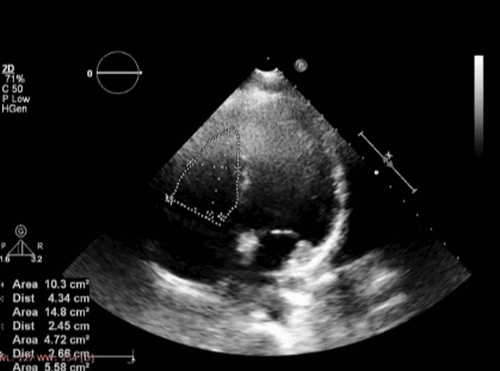

Можно сделать оценки внутренних размеров ПЖ, толщины стенок и ФВ. Функция правого желудочка чувствительна к сократимости миокарда, преднагрузке и постнагрузке, а также к сократимости ЛЖ, вкладу межжелудочковой перегородки и внутриперикардиальному давлению. Анализ функции правого желудочка должен учитывать все эти факторы, а сама по себе ФВ может быть недостаточно чувствительным показателем к этим факторам. Правосторонняя сердечная недостаточность связана с расширенным гипокинетическим ПЖ. Если правый желудочек имеет такой же размер или больше, чем ЛЖ во всех позициях, то это отклонение от нормы. Обратите внимание, что даже в самых опытных руках адекватное эхокардиографическое исследование правого желудочка может быть получено только примерно у 50% пациентов. Новые методы трехмерного эхо-сигнала улучшили оценку структуры и функции ПЖ.